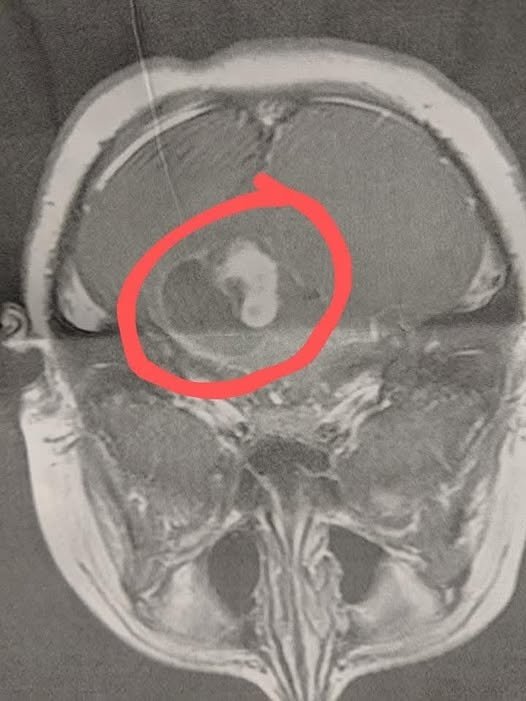

At the office, she showed me the scan — a large mass in my son’s brain with fluid surrounding it. My world stopped. Within hours, we were at Duke University Hospital. My son underwent emergency surgery that same day. The operation lasted eight agonizing hours. The neurosurgeon was able to remove about 90% of the tumor, but the remaining 10% was wrapped around his brain stem and too dangerous to remove.